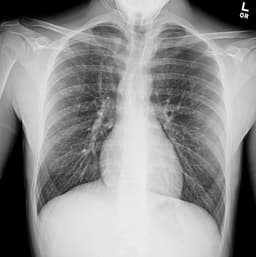

- Multi-center open-label non-inferiority trial looked at treatment of pneumothorax with a small-bore chest tube versus conservative management with exceptional follow up

- 316 patients ages 14-50 with moderate to large pneumothorax (>32% measured on CXR) were randomized into one of the two treatment arms